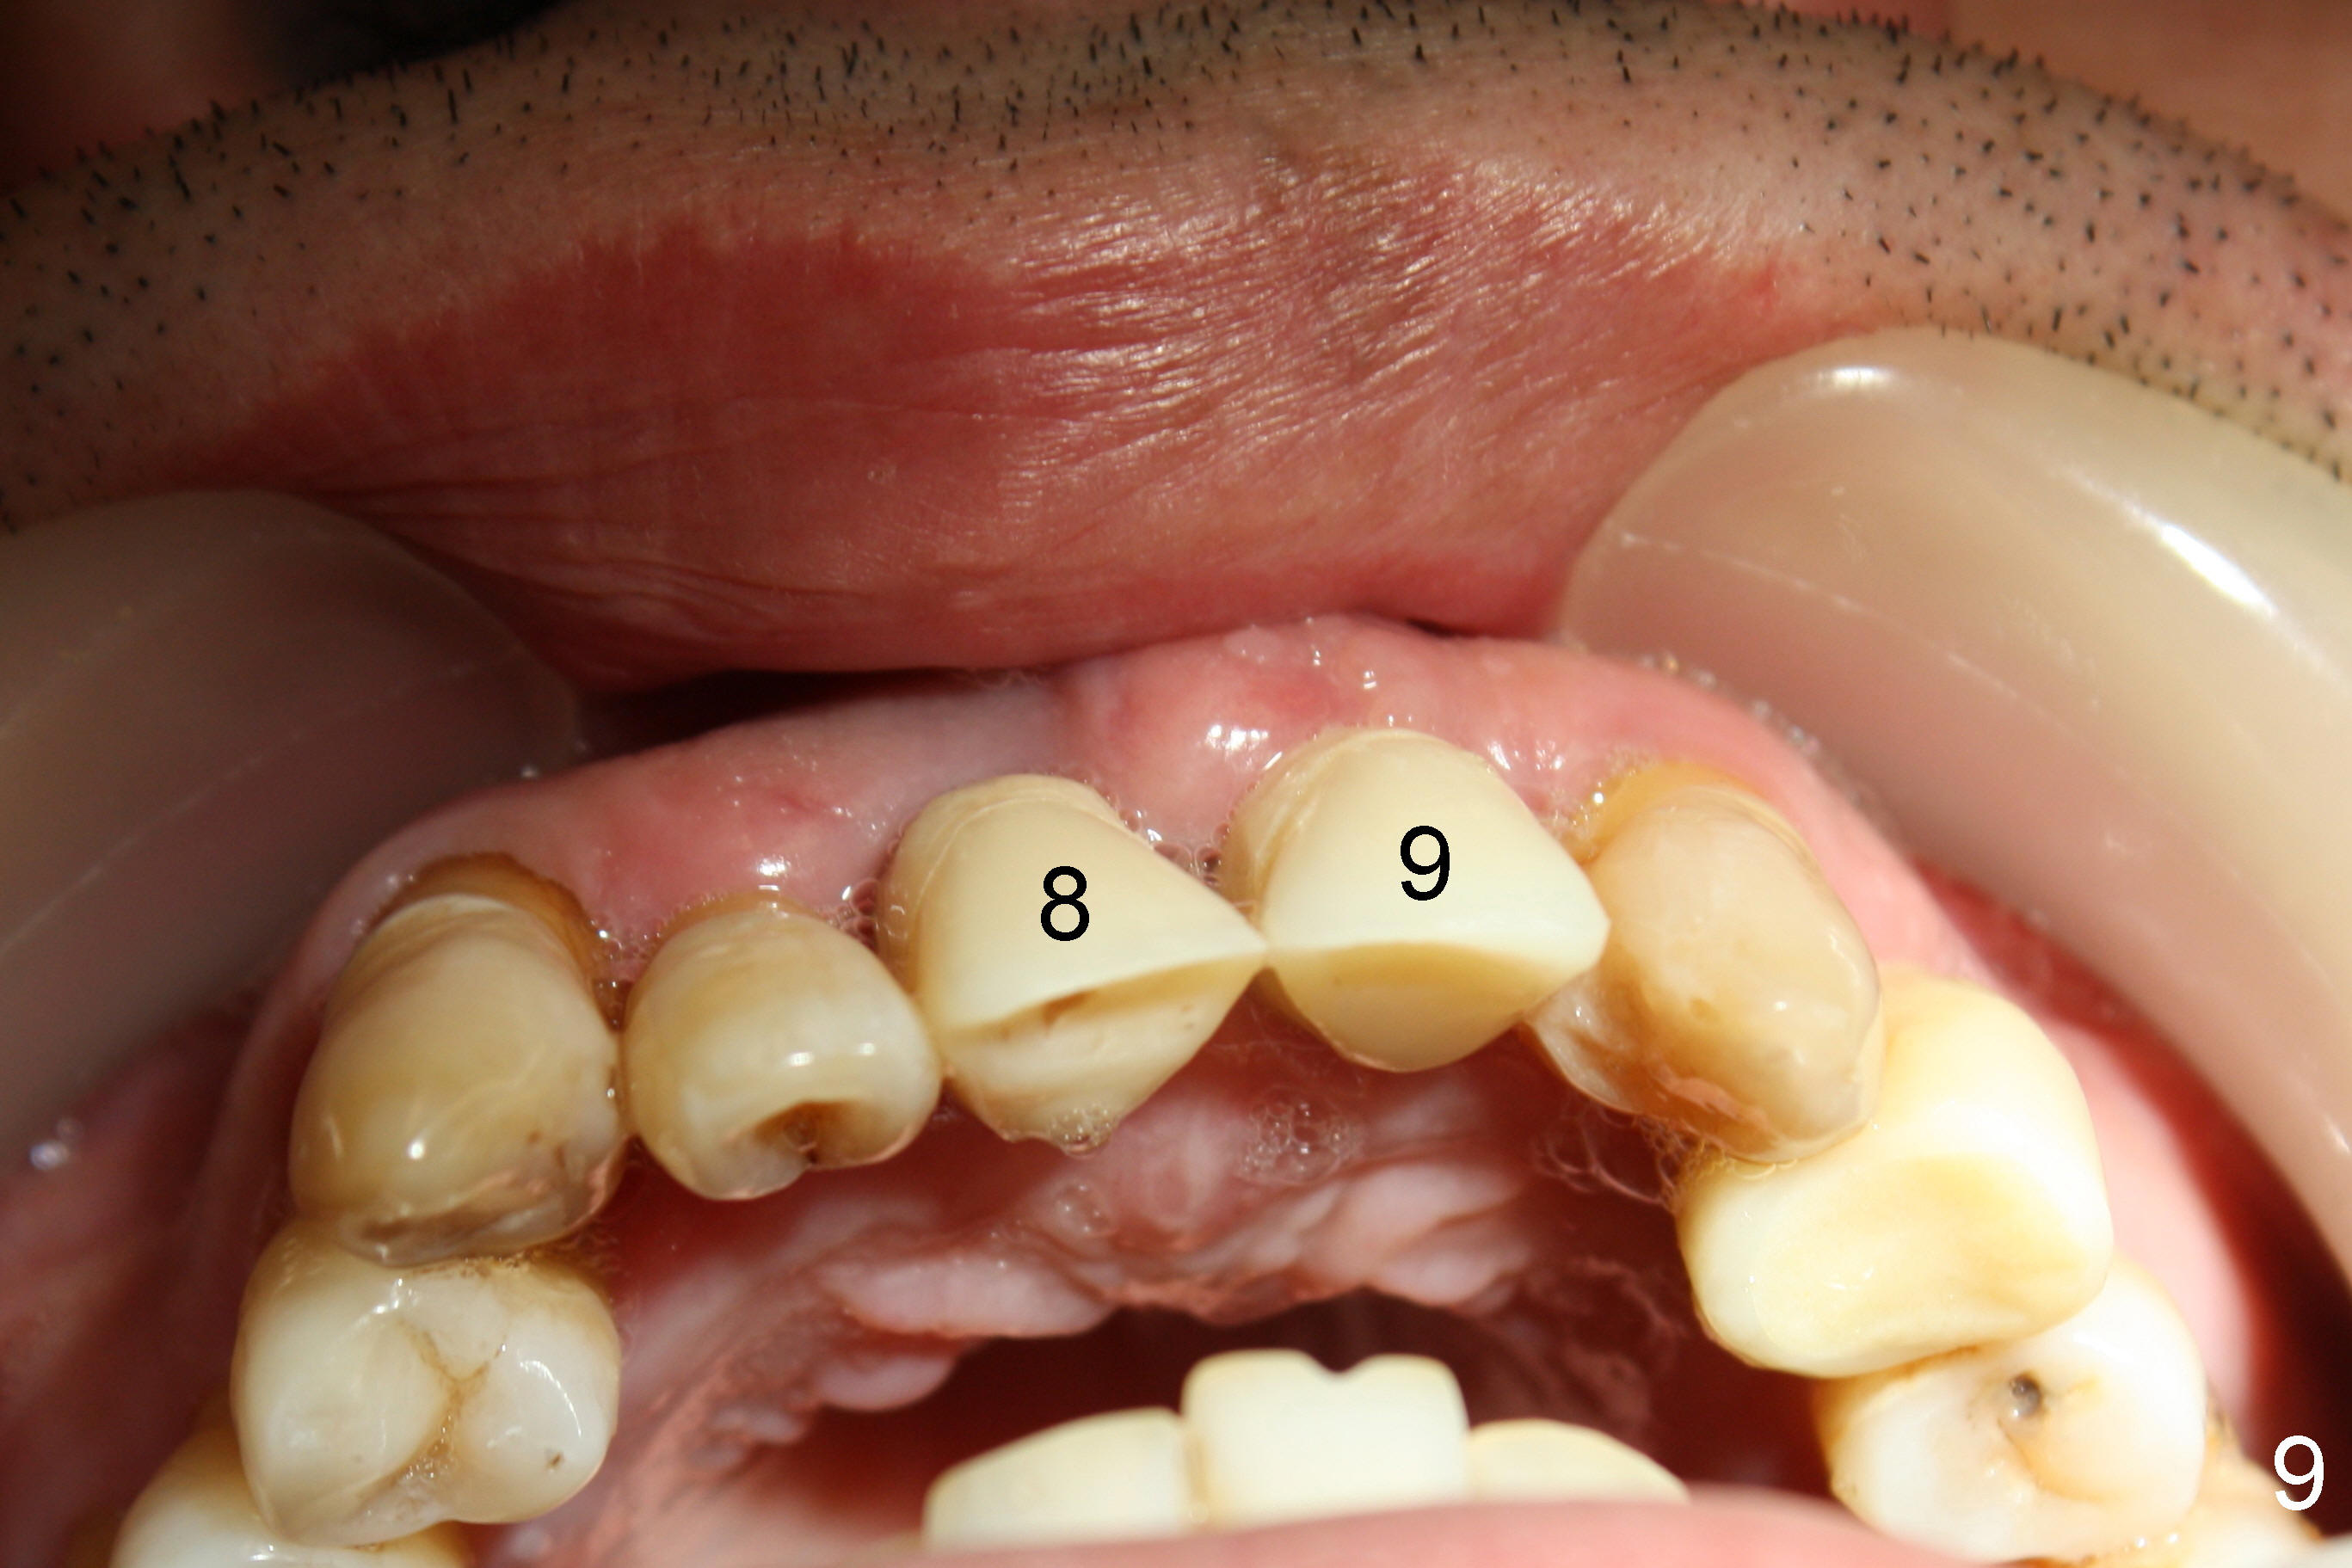

Removal of Two Mesiodens Followed by Immediate Implants and Provisionals

CBCT shows that the two mesiodens, esp. left one, are close to the palatal plate. After removal of the peridontally compromised tooth #8 and the pontic #9 (as compared to Fig.1), the palatal flap is raised to expose the left mesiodens (Fig.2 <; *: incisal foramen).

Following extraction of the two mesiodens, osteotomy starts with pilot drills (Fig.3: 8,9). As planned, these pilot drills go through two of the cortical plates of the mesiodens' sockets (arrowheads).